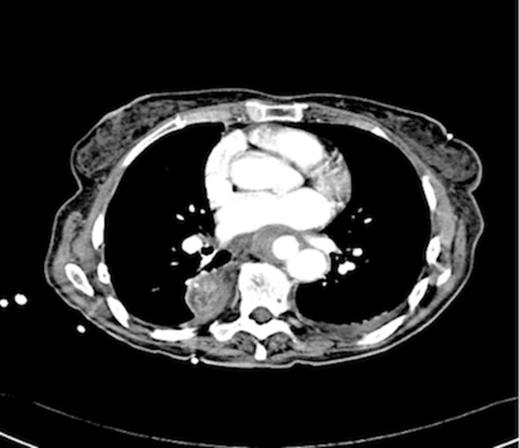

An endoscopy performed four years post-operatively demonstrated two atypical acute gastric ulcers in the distal stomach (figure 1), which were treated with a heat probe (figure 2). Two days later she presented as an emergency in hypovolaemic shock following a large volume haematemesis (haemoglobin of 40g/l). An urgent upper gastrointestinal endoscopy revealed a visible vessel at 35 cm forming part of an expansive mass within the gastric conduit. EUS demonstrated a heterogeneous mass indenting the gastric conduit, containing a strong Doppler signal (figure 3). An urgent computerised tomography (CT) angiogram revealed a Type-A thoracic aortic aneurysm with an enteric fistula (figure 4). The saccular aneurysm of the thoracic aorta was embedded in the gastric conduit. A 28x16cm Valiant® (Medtronic Ltd, Minneapolis, USA) stent was placed in the descending thoracic aorta with good occlusion of the aneurysm. The patient made an excellent recovery and was discharged on the seventh day post stenting.

Post operatively the patient developed a low grade stent infection requiring a prolonged course of antibiotics as an outpatient. Two years after insertion of the stent she remains well with no further gastrointestinal bleeding and follow up endoscopy has shown intact mucosa at the site of fistula. Computerised tomography scanning has demonstrated involution of the aneurysm sac and no endo-leak (figure 5).